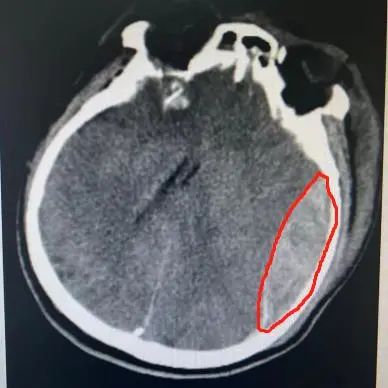

积极抢救后,王先生的血压终于有所上升,立刻为他进行头颅+胸部+全腹部 CT,检查结果显示:他的双侧额骨、颞骨、蝶骨骨折,颅底骨折,颅内积气,左侧颞顶部及右侧顶枕部硬膜下血肿、蛛网膜下腔出血,颈椎 567 锥体横突骨折,右 6-9 肋骨多根多处骨折伴有肺挫伤。

经过 2 个小时紧张的综合抢救后,王先生的血压明显改善,生命体征逐渐稳定,复查头颅 CT,检查结果显示,脑出血明显增多伴有中线偏移,脑疝形成。